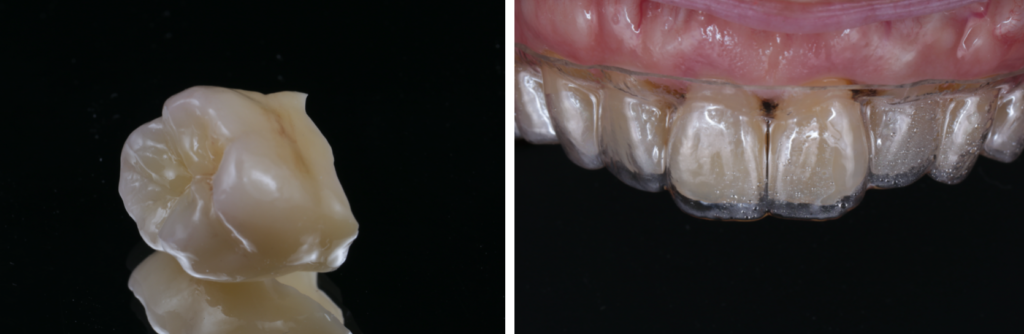

銀歯を白くする治療で失敗しないために──“接着”と“噛み合わせ”が運命を決める理由

「銀歯を白くしたい」「口を開けたときに金属が見えるのが気になる」このようなお悩みからセラミック治療を検討される方は非常に多くいらっしゃいます。とくに40代以降の女性の患者さまは、見た目はもちろん、“健康面として歯を…

保険のCR処置のリスクと

自由診療レジン治療が選ばれる本当の理由

虫歯治療で行われる**保険のCR処置(コンポジットレジン修復)**は、「白く治る」反面、